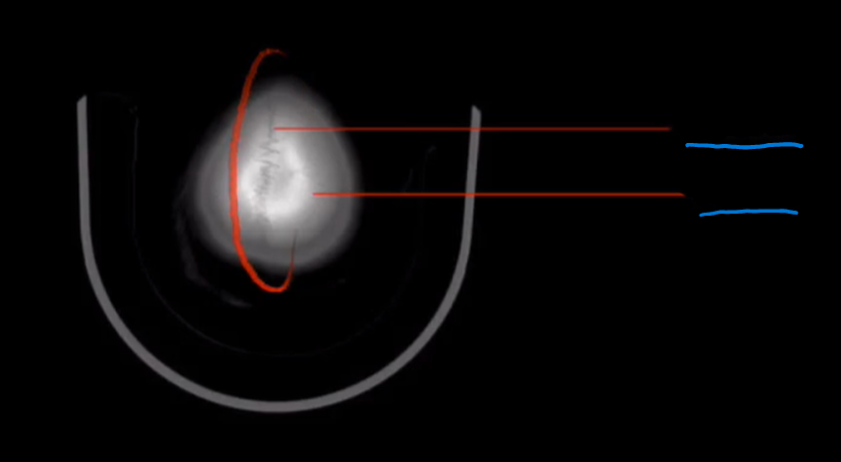

What is the landmark of # 1 called?

Frontal Bone

What is the landmark # 2 called?

Frontal Sinus

What is landmark # 3 called?

Orbital roof